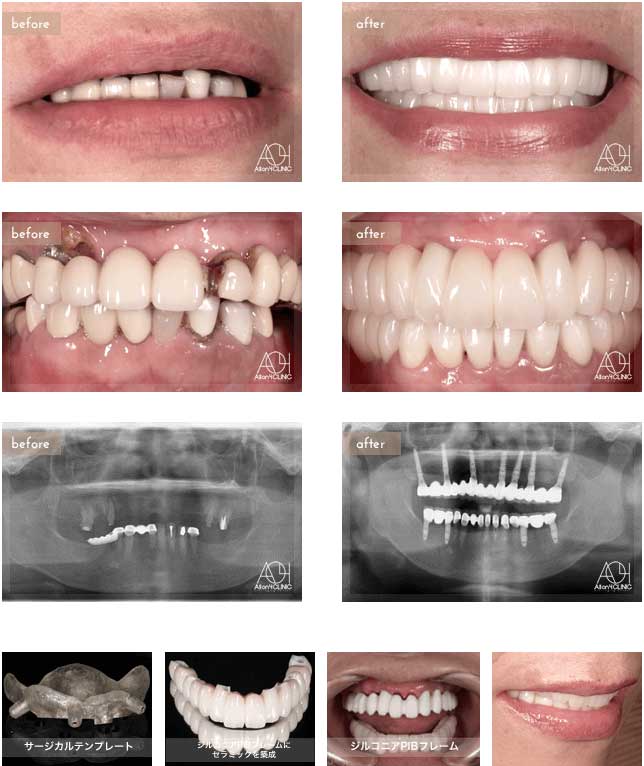

Treatment : All-on-4 non gum

- Upper All-on-4

- Lower implant

Age : 42 Sex : 女 Y.R

| 主訴 | 歯がボロボロなのは分かっているが、時間的な余裕が無いことと歯科に対する恐怖心から、悪いままの状態を放置してしまった。人前でおもいっきり笑いたいので意を決して来院。 |

| 治療内容 | ガイデッドサージェリーにてインプラント埋入。歯槽骨が残っていたため歯冠形態のみ(ガム無し)の補綴 |

| 治療費(総額) | ¥3,500,000(税抜) 『モニター割引適用』 |

| リスク | 治療後の口腔管理が不適切な場合、埋入したインプラント周囲に感染・炎症を起こし、脱落する可能性がございます。 |